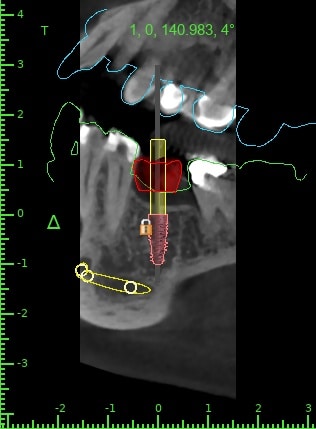

here a guided surgery case where a lower molar was replaces by an implant ,flapless ,thanks to a good digital planification and a realisation of a surgical guide